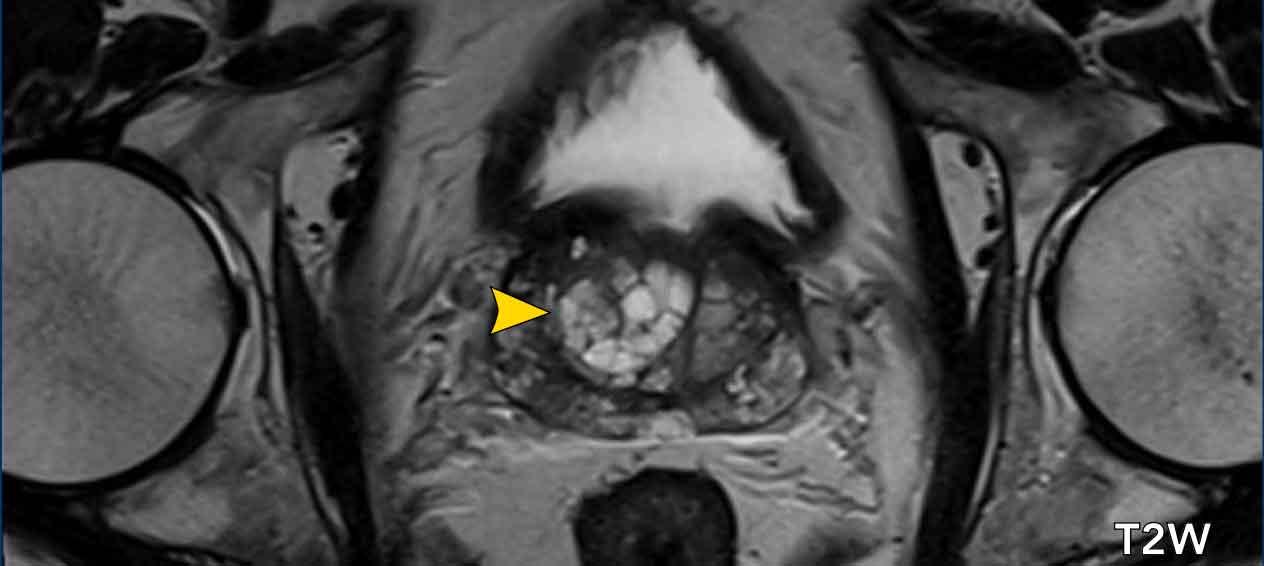

Bệnh nhân nam 70 tuổi được chuyển đến với PSA tăng 9ng/ml, mật độ PSA 0,10.

Điểm PI-RADS 5 được gán cho một vùng giảm tín hiệu ở vùng ngoại vi bên phải tại phần giữa tuyến, có hạn chế khuếch tán (mũi tên đen).

DCE cho thấy ngấm thuốc mạnh và ngoại vi của tổn thương (đầu mũi tên).

Sinh thiết được thực hiện và kết quả mô bệnh học cho thấy hình thành ổ áp xe.

Ngấm thuốc ngoại vi và hạn chế khuếch tán là những phát hiện hình ảnh điển hình của ổ áp xe.